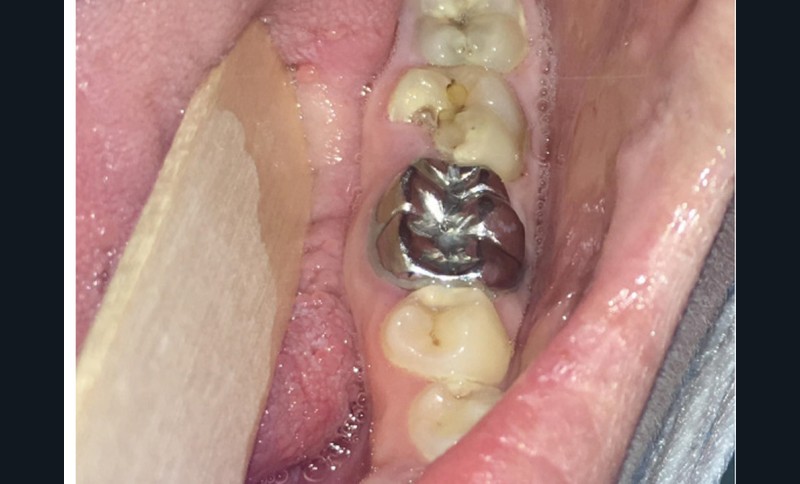

Dans le bilan avant mise en place du traitement, les recommandations, notamment de rhumatologie, indi-quent la réalisation d’un bilan dentaire et la mise en œuvre des soins nécessaires [1]. Cela a pour but d’identifier les foyers infectieux en présence et de les prendre en charge avant que le traitement ne débute, donc avant que le patient présente un risque infectieux accru (fig. 2).